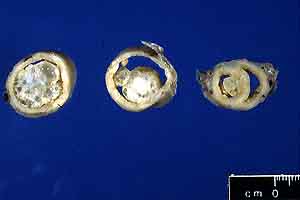

- Case 21-4. Uterus. Extending from the uterine mucosa

- Gross Pathology: The formalin-fixed uterus was moderately

distended and filled with opaque brown fluid. The uterine horns

contained six broad-based to pedunculated endometrial nodules

ranging from 0.5 cm to 2 cm in diameter (gross photo of cross-sectioned,

formalin-fixed uterus). Nodules were located throughout the

uterine horns from near the uterine bifurcation (section on the

right) to the tips of the horns (section on the left).